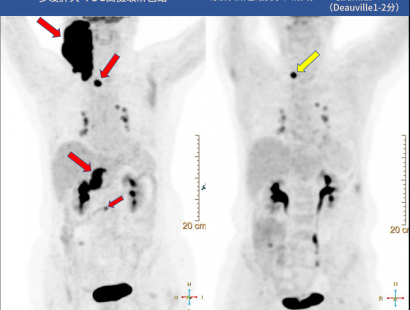

七十多岁的张奶奶(化名),10年前做了乳腺癌手术。去年发现颈部淋巴结肿大,活检结果为弥漫大B细胞淋巴瘤,采取化疗保守治疗,为了监测治疗效果,做派特CT检查。

从派特CT影像可以看到:

化疗前,张奶奶淋巴多发肿大,淋巴结FDG摄取高;化疗4个疗程后,原肿大淋巴结变小、消失,FDG摄取减低,但是又发现了新发增大且FDG摄取高的淋巴结。

通过派特CT精细准确的扫描,给张奶奶下一步治疗方案的制定提供了宝贵信息。